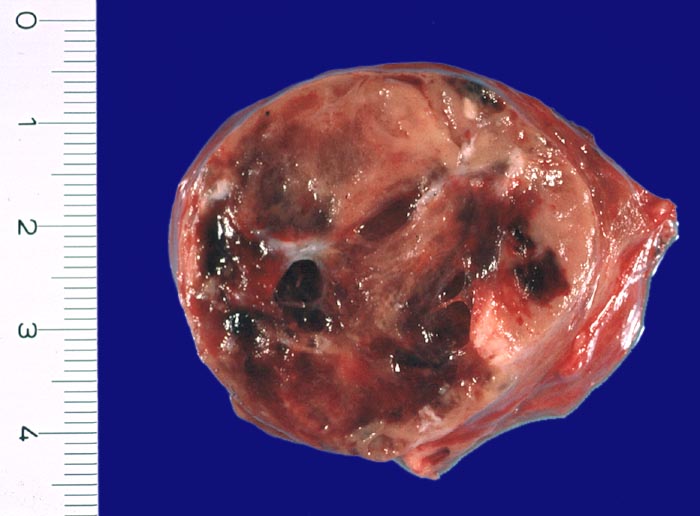

• Anschnitt eines grossen mikrofollikulären Knotens (autonomes Adenom) mit angedeuteter Kapsel und zentraler Einblutung. Oben zwei weitere kleine Satellitenknoten.

• Kompression des angrenzenden Schilddrüsenparenchyms. Dieses besteht aus grossen Follikeln mit kubischem oder abgeflachtem Epithel und reichlich kompaktem dunklem Kolloid in den Follikellumina.